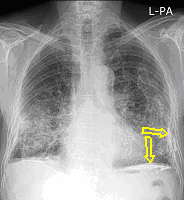

20. Miliary lung metastases. HRCT, coronal reconstruction:

60 year old man, secondary pulmonary lesions due to kidney tumor, underwent target therapy.

Lobulated nodule in the left lung, associated with the pleura dorsobasally.

Lobectomy because of right lung adenocarcinoma, (brain metastasis). (by the contribution of Zsuzsanna Monostori, MD, PhD)